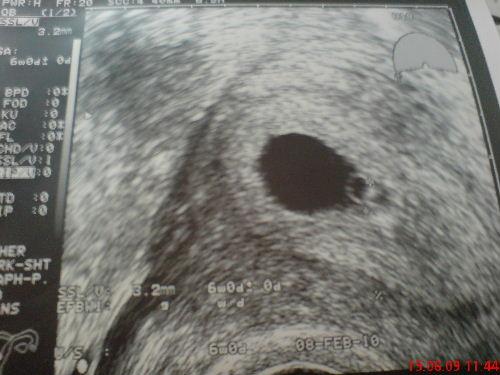

Hallo Mädels! Bin jetzt von FÄ zurückgekommen...hab ja heut Blut abgenommen bekommen, Urin untersucht und Blutdruck gemessen.....tja, und beim Ultraschall ist auch alles ok, leider konnte man das Herzchen noch nit schlagen sehen, aber ganz sicher beim nächsten Termin in 4 Wochen Wollt euch daher noch ein viele Viren dalassen und euch mein Bildchen zeigen...Liebe Grüsse PPPPPPPPPPPPPPPPPPPPPPPPPPPPPPPPPPPPPPPPPPPPPPPPPPPPPPPPPPPPPPPPPPPPPPPPPPPPUUUUUUUUUUUUUUUUUUUUUUUUUUUUUUUUUUUUUUUUUUUUUUUUUUUUUUSSSSSSSSSSSSSSSSSSSSSSSSSSSSSSSSSSSSSSSSSSSSSSSSSSSSSSSSTTTTTTTTTTTTTTTTTTTTTTTTTTTTTTTTTTTTTTTTTTTTTTTTTTTTTTTTTTTTTTTTt

Bild zu zurück von FÄ - Kinderwunsch - was tun, um schwanger zu werden?